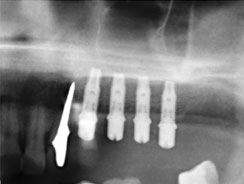

Имплантация

Одноэтапная имплантация